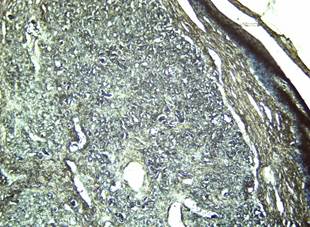

Durante la segunda etapa de la técnica histoquímica donde se lava la muestra y se aplica fucsina ácida y ácido pícrico saturado, se observan numerosos fibroblastos con núcleos azules (Figura 5), mientras que las fibras colágenas toman una tonalidad gris o negra. Se observa proliferación de fibras elásticas coloreadas también de negro pero más delgadas que las colágenas. En esta figura se observa que las fibras colágenas predominan en la periferia de la lesión, mientras las elásticas se concentran alrededor de los vasos sanguíneos, típico de los fibrohemangiomas. La gran proliferación de fibroblastos indica la reactividad del tejido conjuntivo ante la presencia de un agente etiológico, lo cual conduce a la intensa proliferación de colágeno e instaurándose en la dermis escrotal un proceso fibrótico. (Figura 5). Este resultado es compatible con lo reportado por Méndez Rodriguez et al. (2021).

Figura 6. Hiperqueratosis epidérmica y en la dermis se observan numerosos fibroblastos (núcleos azules), fibras colágenas, más abundantes hacia la periferia de la lesión, y fibras elásticas (más delgadas), alrededor de los vasos sanguíneos, todas con tonalidad gris o negra. ColoraciónTricrómico de Van Gieson 4 X.

Elaboración: Los autores.

Con las técnicas histoquímicas se evaluó la cantidad y distribución de las fibras colágenas y elásticas de la zona dérmica en el papiloma escrotal porcino. En todas las porciones del tejido dérmico papilomatoso se encontraron fibras elásticas dispuestas en todas direcciones, siguiendo la misma distribución de las fibras colágenas. Se encontraron diferencias significativas entre la cantidad de fibras colágenas y elásticas presentes en las zonas evaluadas, lo que sugiere que el rol de las fibras colágenas es preponderante para adaptarse a las nuevas condiciones funcionales de la formación papilomatosa. Así mismo estos resultados muestran que intercalado con el tejido conjuntivo denso aparecen zonas de tejido conectivo laxo con escasa cantidad de fibras colágenas (Figura 6).